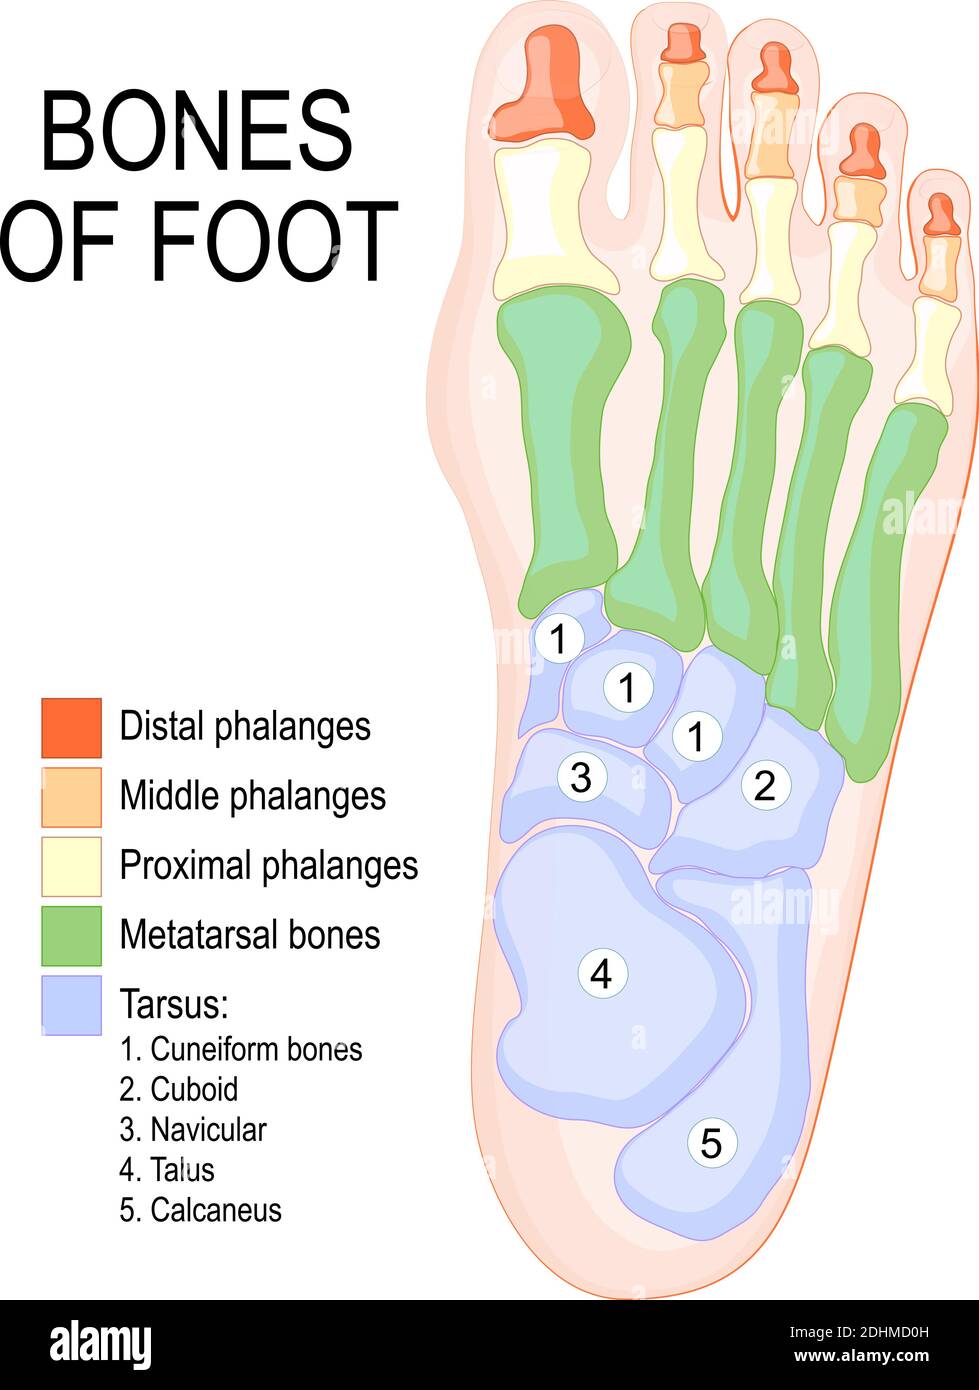

RF2DHMD0H–OS du pied. Anatomie humaine. Le schéma montre l'emplacement et le nom de tous les os du pied.